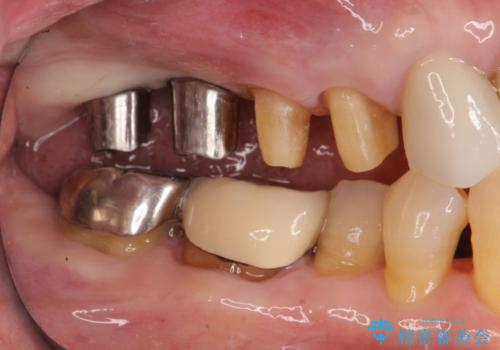

- 数年前にいれた右上のブリッジが、「ぐらついて痛い、噛めない。」と改善を希望され来院されました。

X線写真より、咬合力負担能力に十分で無い親知らずを使用した長いブリッジが装着されており、力の負担に耐え切れずぐらつきが増加してきた状態です。

親知らず、ブリッジを抜去・撤去しインプラントを用いた咬合機能回復を行っていくこととしました。

- 123.2万円(インプラント×2・チタンカスタムアバットメント×2・ジルコニアクラウン×4・仮歯×4)費用は治療当時の料金となります